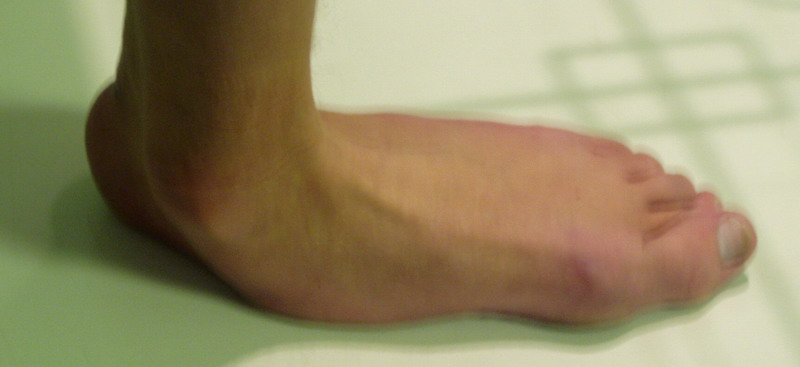

Пациент 15 л., болезнь Литтля, спастический нижний парапарез, интеллект высокий. Ребенок настроен на активный образ жизни. С недавнего времени начал ходить без дополнительной опоры. Появилась проблема с левой стопой - во время ходьбы опора приходится на смещенную кнутри таранную кость.

Может образоваться болезненный натоптыш или язва.Общепринятой операцией является трехсуставной артроде с мобилизацией таранной кости. Выполнять такую операцию у спастика и в раннем возрасте проблематично. Родстьвенники тем более готовы материально и морально осуществить хирургическое лечение за рубежом, если оно показано и возможно.Предпочтительно в Австрии и Германии. Если кто-то посоветует координаты таких клиник - были бы признательны.